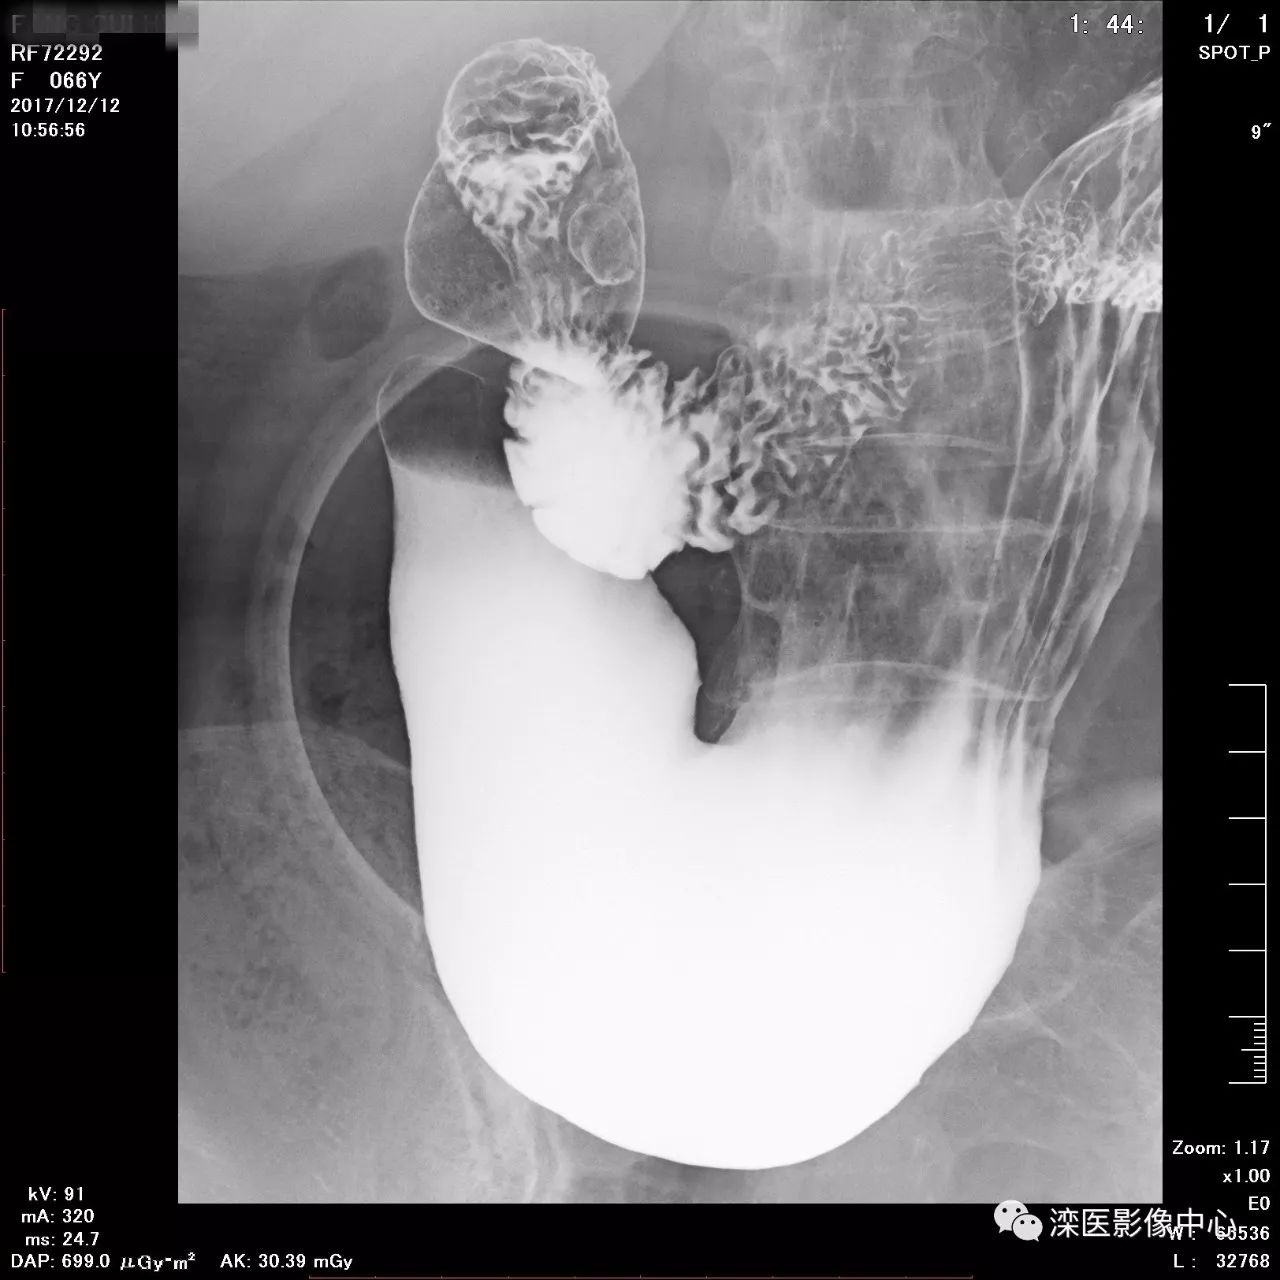

(以上图像是患者立位+卧位,通过变换体位,多角度显示了贲门胃底、胃体、胃大弯、胃小弯、胃窦、幽门及十二指肠球部、降部、水平部、升部的粘膜像和充盈像。本例患者女性,66岁,此次检查可以清晰显示胃小区结构,检查中发现患有慢性胃炎、胃下垂、十二指肠降部憩室)